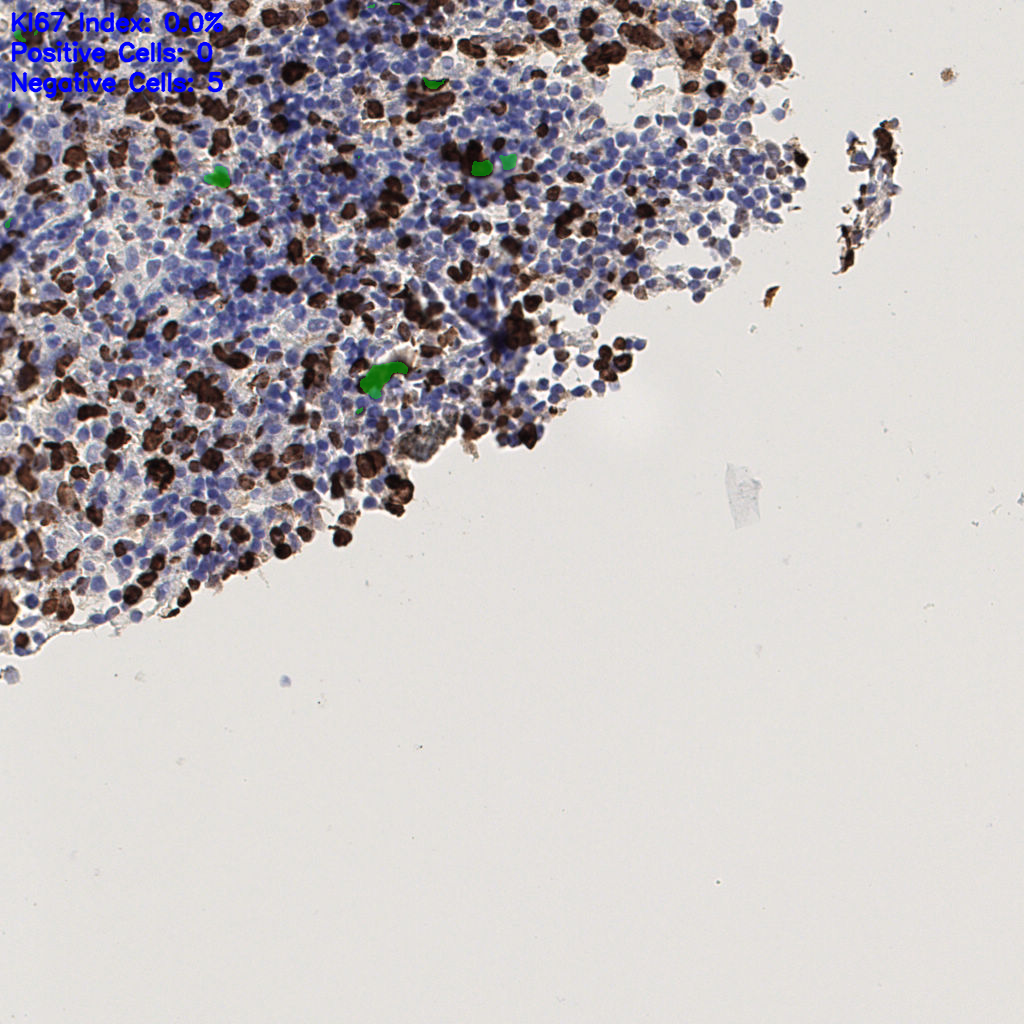

7.85%

Ki67 指数

阴 1104

阳 94

切片统计

总切片

1953

有效

288

已标记

有效率

15%

标记后

标记前